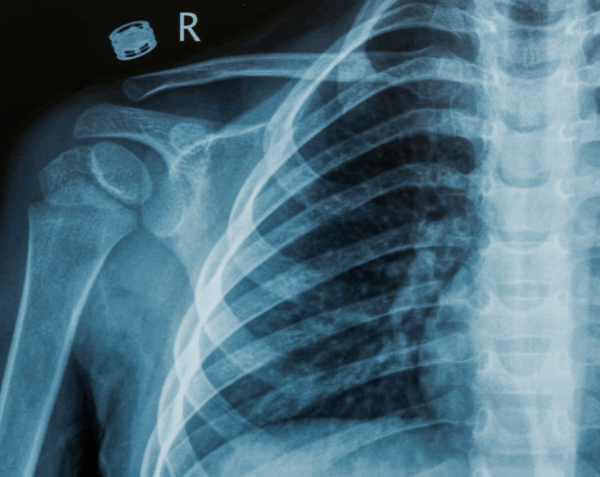

A right rib series X-ray provides a detailed set of images focused on the right side of your rib cage. Physicians use this test to detect fractures, dislocations, bone abnormalities, or complications affecting the lungs and chest wall. At Desert Mobile Medical, we deliver this vital diagnostic service directly to you with mobile X-ray technology, ensuring comfort, privacy, and fast results—without the hassle of traveling to a hospital or urgent care.

A rib series typically includes multiple images at different angles, giving physicians a comprehensive view of the rib structure and surrounding chest area.